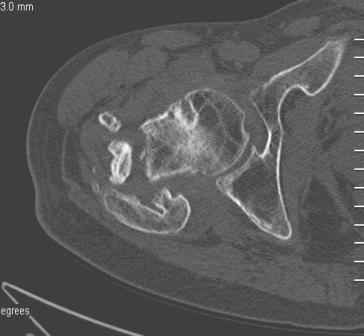

Сросшийся со смещением чрез-подвертельный перелом

Больной Н. 44 года травма 1,5 года назад июнь 2008 года чрез-под вертельный перелом правого бедра. Во время лечения у больного развился алк. делирий, проводилось консервативное лечение перелома.

Беспокоят боли, укорочение конечности.Укорочение 3 см. Ногу поднимает, сгибание ограничено, ротационные движения в полном объеме.На КТ перелом сросся за счет костной мозоли.Что делать?

Протез? Если «да» Можно ли обойтись стандартной ножкой Corail?

Или межвертельная остеотомия?

Уважаемый Глеб! Укорочение наверное побольше, да и наружно-ротационная установка скорее всего присутствует. Суставная щель прекрасная, головка живее всех живых. Ратую за подвертельную с латерализацией: исключает нарушение механической оси («исключает вальгус в коленe»), максимально удлиняет без натяжения m.iliacus. Для иллюстрации остеотомия-переделка (слава богу не автопеределка) у мужчины 65 лет.